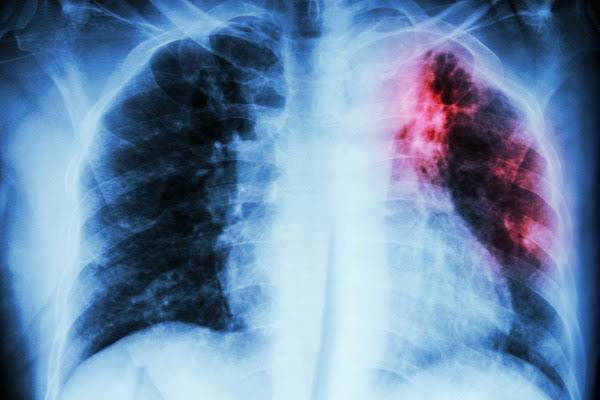

A tuberculose é uma doença infecciosa e transmissível, causada pela bactéria Mycobacterium tuberculosis, também conhecida como bacilo de Koch. A doença afeta principalmente os pulmões, embora possa acometer outros órgãos. A forma extrapulmonar, que afeta outros órgãos que não o pulmão, ocorre mais frequentemente em pessoas vivendo com HIV, especialmente aquelas com comprometimento imunológico.